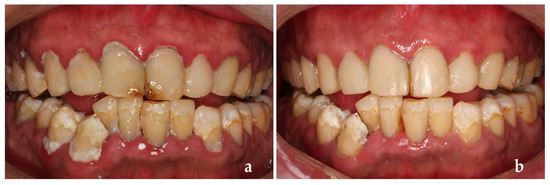

Finally, the patient was followed up for observation. The modified USPHS standard was used to evaluate the quality of restorations in this software. One year after treatment, we found that the aesthetic effect, margin fitness and color matching of the restorations were excellent. The patient had no secondary caries, but we found the poor retention of a restorative filling in tooth #22 (Figure 5a,b). It can be seen that one year after treatment, the patient’s dental health had improved, and we dealt with the problems we found in time (Figure 5c,d). Then we reassessed his caries risk and it dropped from high risk to medium risk. So, we adjusted his caries management (Figure 6a–c).

Figure 5.

(a,b) One year after treatment; (c,d) After the dentist dealt with the new problem in time.

USPHS was used to evaluate the restorations again 2 years after treatment, this time we found secondary caries in the patient’s teeth (Figure 7). We removed secondary caries and restored the cavity again in time, then he reassessed the caries risk routinely, which was still at medium risk.

Figure 7.

Two years after treatment.

However, after this return visit, the patient was lost to follow-up for 3 years. Three years later (5 years after the first treatment), the patient came back with dental plaque covering the whole tooth surface, severe periodontal inflammation, many secondary caries and the retention, margin fitness and color matching of the restorations were poor (Figure 8a). Retreatment at this time could not achieve a perfect therapeutic effect (Figure 8b) and the reassessment of his caries risk this time was high risk again.

Figure 8.

(a) Five years after treatment; (b) Retreatment completed.